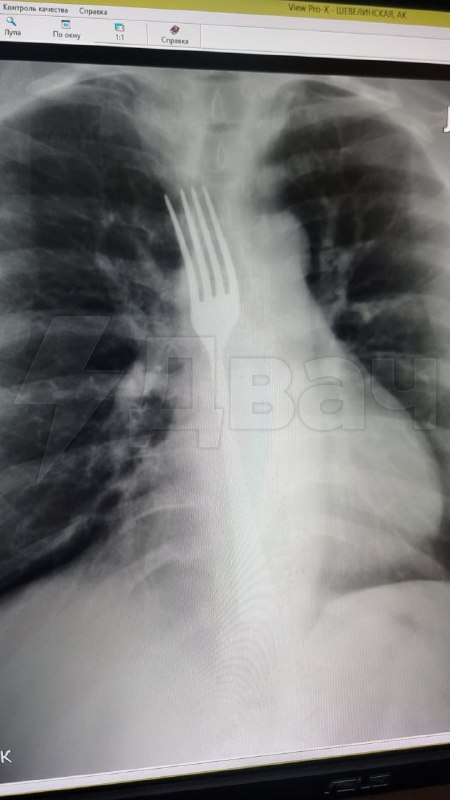

Женщина случайно проглотила вилку, пытаясь вызвать рвоту

Не найдя ничего лучше, витебчанка попыталась вызвать рвоту вилкой, но из-за неловкого движения она проглотила прибор целиком.

Девушке срочно вызвали скорую, и её доставили в больницу на операционный стол, где хирурги разрезали ей живот и извлекли вилку.